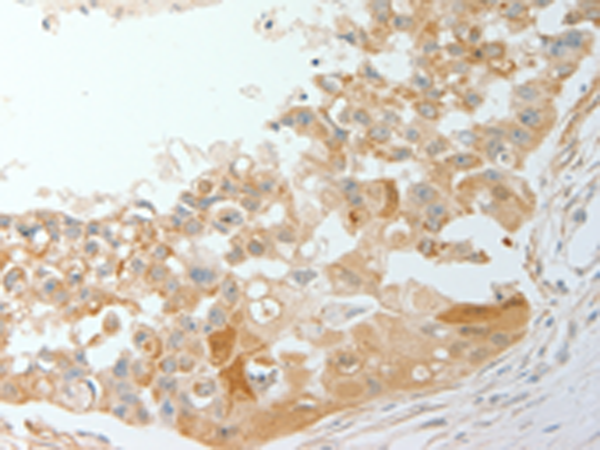

IHC positive control:

Human breast cancer and Human cervical cancer

ELISA, IHC